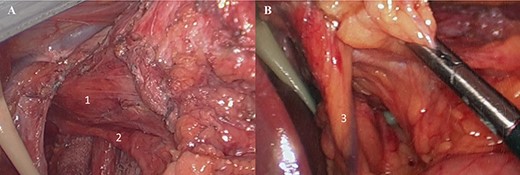

The patient underwent an elective laparoscopic surgical revision. Intraoperatively, majority of the SG had herniated into supradiaphragmatic position through the diaphragmatic esophageal hiatus and had a partial organoaxial volvulus (Fig. 2). Lysis of adhesion was carried with full mobilization of the SG and distal esophagus were achieved. The intrathoracic SG was reduced followed by the excision of the hernia sac with preservation of anterior and posterior vagus nerves and the left gastric artery (Fig. 3). The esophageal hiatus diaphragmatic defect was closed with four figure of eight stitches posterior to the esophagus using braided zero polyester (Fig. 4A). A relative narrowing of the mid portion of the SG at the incisura and an excess of gastric fundus was present. A 4 cm long gastric pouch was created in a standard fashion and the remnant of the SG was excised (Fig. 4B and C). Then a standard jejuno-jejunostomy (J-J) was done with a biliopancreatic limb of 60 cm and alimentary limb of 100 cm and the gastro-jejunal anastomosis was created using a 25 mm/4.8 mm circular stapler and reinforced with Lambert sutures of 3–0 polyglactin (Fig. 4D). The J-J and Peterson mesenteric defects were closed. Intraoperative leak test was negative.

(A) Laparoscopic view of gastric sleeve herniation through esophageal hiatus (1. right crura of diaphragm covered by gastro-hepatic ligament just lateral to esophageal hiatus, 2. gastric antrum); (B) laparoscopic view of dissected esophageal hiatus (3. caudate lobe, 4. right crura of diaphragm, 5. left crura of diaphragm, 6. aorta, 7. distal esophagus).